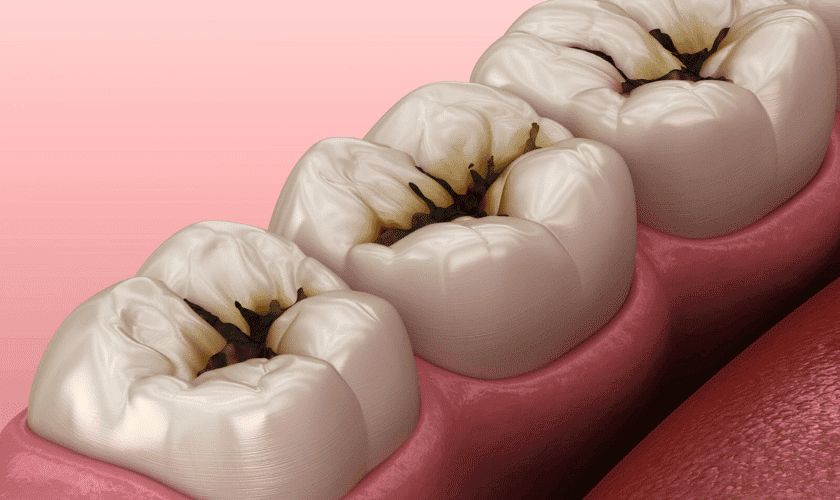

Tooth decay is the gradual damage to the surface of a tooth caused by bacteria. It starts when plaque forms on your teeth. The bacteria in plaque produce acids that slowly erode the enamel. Over time, cavities (holes in the teeth) appear.

Stages of Tooth Decay

- Enamel decay – The outer surface weakens.

- Dentin decay – Bacteria spread deeper, causing pain.

- Pulp damage – The nerves inside the tooth become infected.

- Abscess – Infection spreads, sometimes causing swelling in the face.